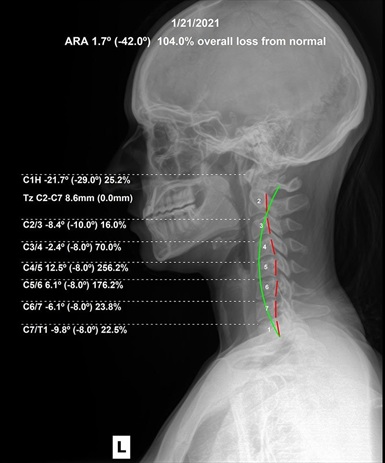

Your spine is made up of small bones called vertebrae, separated by soft discs that cushion movement. If a vertebra shifts out of place (due to injury, stress, or poor posture), it can put pressure on these discs and pinch nearby nerves. This is called a subluxation.

Subluxations can cause nerve irritation, pain, inflammation, and even interfere with how your body communicates with itself—leading to a wide range of symptoms in different areas of the body.